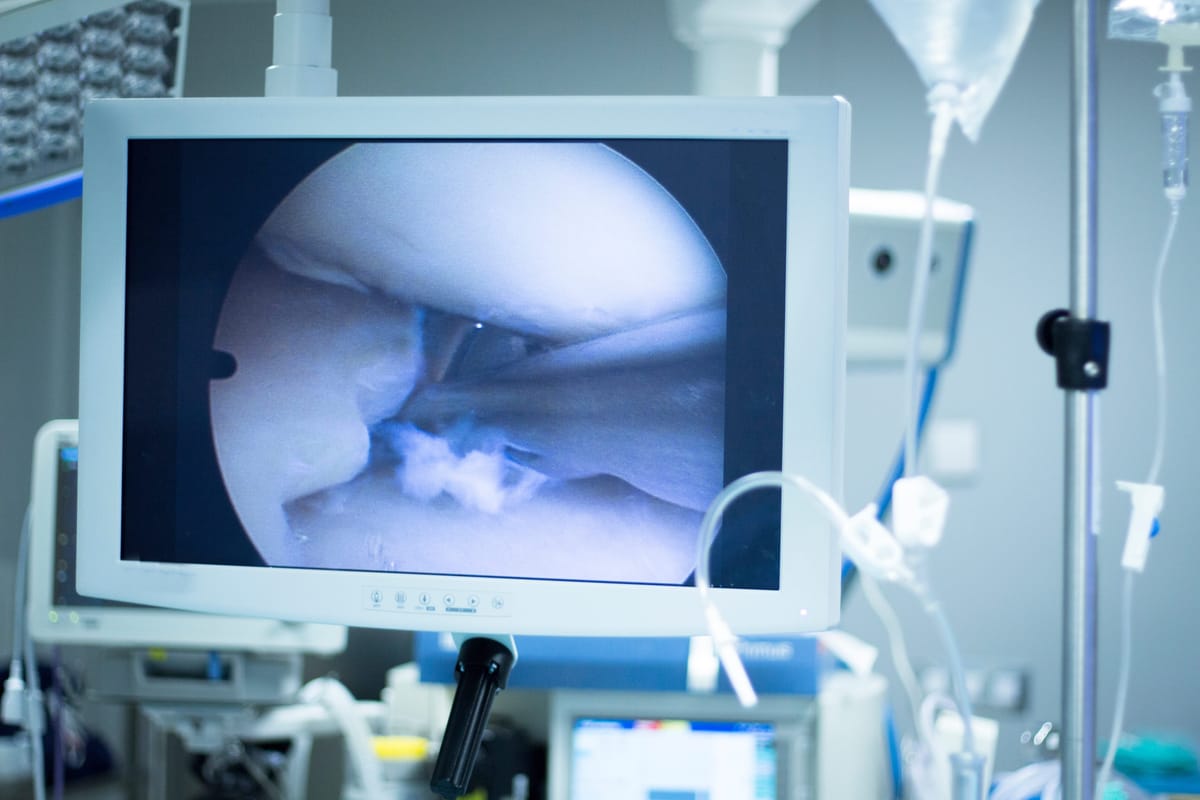

Cirurgia da Mão